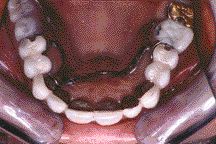

Maintaining Proper Access of the Maxillary and Mandibular Ridges During Impression Making

It has been reported in several published articles that prosthodontic success is contingent on patient cooperation both during treatment and after care. As dentists we all know that one of the most difficult procedures is trying to make an impression on the edentulous patient. Some patients have extremely strong muscles and we are fighting to … Read more